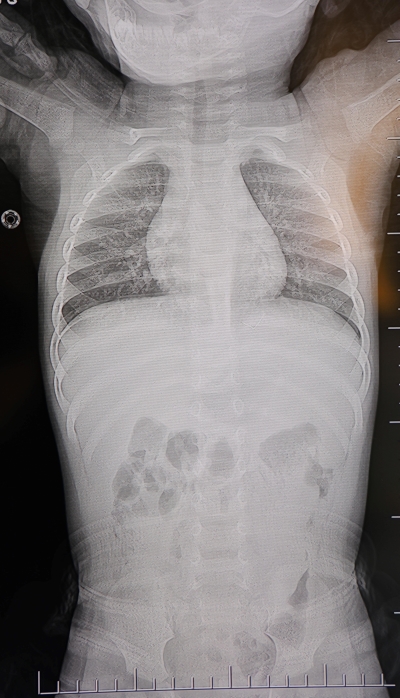

Aile, son olarak HG Hospital’e başvurdu. Beyin ve Sinir Cerrahisi Uzmanı Prof. Dr. İdris Altun tarafından yapılan tetkiklerde, yabancı cismin cilt altında, omurilik kanalına çok yakın bir bölgede bulunduğu ve akciğer zarına doğru ilerlediği tespit edildi.

Operasyonda çıkarılan cismin, ince zımba teline benzer metal bir tel olduğu ve yaklaşık 2 santimetre uzunluğunda bulunduğu belirlendi. Bebek, ameliyatın ardından aynı gün taburcu edildi.